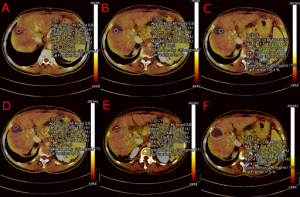

E' stata adoperata sempre la stessa macchina dotata di detettori a 128 strati (TC SOMATOM Definition Edge di Siemens Healthcare, Erlangen, Germania) con una risoluzione spaziale di 0,30 mm, dotata di tecnologia Twin-Beam. L'analisi delle immagini a doppia energia è stata eseguito tramite il software syngoCT Workplace VB20 di Siemens Healthcare GmbH (Erlangen, Germania) con l’applicativo “Liver VNC Application Class” per l'analisi delle scansioni TC eseguite in fase portale TBDE. Sulle immagini VNC, un radiologo esperto ha tracciato da 3 a 6 regions of interest (ROI) per ciascuna lesione (superiore, inferiore ed in base all'estensione da 1 a 4 ROI centrali) con area di 1 cm^2, una ROI centrale più estesa che comprendesse 5 mm di parenchima epatico non-ablato tracciato sullo stesso piano della ROI centrale di 1 cm^2 (FIGURA 2-3-4-5). Nel tracciare le ROI si è posta la massima attenzione nell’evitare strutture peri-lesionali e i vasi sanguigni. Per ogni ROI tracciata è stato estrapolato il valore quantitativo della densità dello iodio in mg/dl considerando anche valori negativi (ovvero privi di impregnazione di mezzo di contrasto). Allo stesso radiologo è stato poi richiesto di compilare in cieco, una scheda qualitativa che decretasse se il trattamento effettuato fosse "completo" o "incompleto" nelle TC analizzate (TABELLA 1).

FIGURA 2. Analisi VNC sul piano assiale. Sono ben visibili le 4 ROI centrali e la ROI centrale con incluso un bordo di 5mm nel parenchima epatico circostante.

FIGURA 3. Analisi VNC in proiezione sagittale, in cui si evince la distanza cranio-caudale tra le ROI superiore, centrali e inferiore.